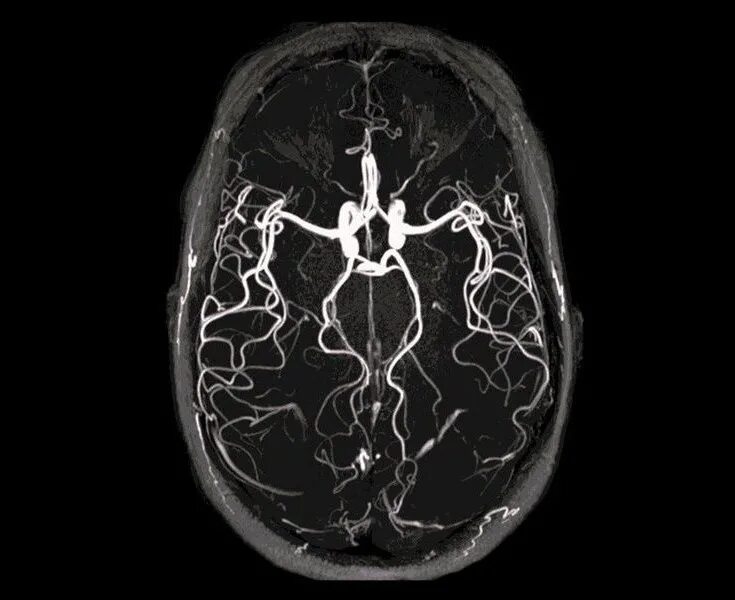

Томография сосудов головного мозга